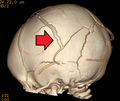

-

3D CT reconstruction showing a skull fracture in an infant